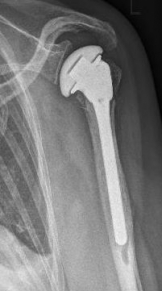

Picture: A subcapital upper arm fracture was treated with a prosthesis. The humeral head was completely removed and replaced by the prosthesis. This is anchored in the upper arm with the prosthesis shaft.